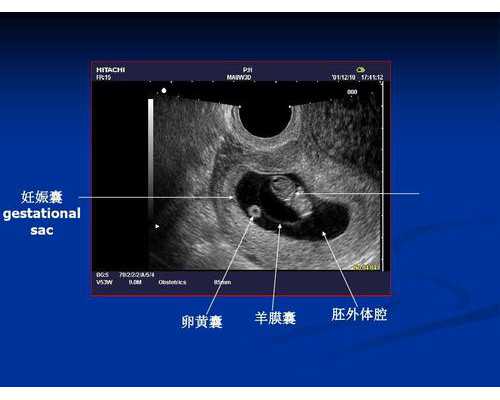

我们的港澳通行证还有2个月就快过期,就赶紧联系那边验血顾问,说是6周B超能看到心管搏动就可以去香港验血看男女了,那时候因为备孕的事儿已经好久没有出远门了,所以格外高兴。

结果预约的人跟说,要我把B超单发给她看下,是否达到检测标准,我说我算的时间就是对的呀,结果我去医院做B超的时候,才发现还看不到心管搏动,根本没有达到检测的标准,原来自己的推算日期跟人家化验所要检测的时间完全是对不上的。

后来按照预约客服的推算的日期,再到医院B超的时候,6周能看到心管搏动了,算的真的是刚刚好,所以建议大家,按照预约客服的要求来,自己的算法有时真不对,最后导致结果不准确就不好了,因为没达到周期,是怕检测不出来的哦。

第1步,要确认怀孕,并且有胎心胎芽。

第2步,确认怀孕周期:孕7周,胎芽长度达到10mm或以上。

每一个备孕成功的孕妈,在得知自己怀孕之后都会非常欣喜,同时也对胎宝宝充满了好奇,希望通过做B超进一步确定怀孕的情况,以及提前知道肚子中怀的宝宝是男孩还是女孩。

一般而言,怀孕后的第一个B超可在妊娠6-8周的时候做,但很多人想早一点知道,难免会将B超时间提前,便有人问:怀孕40天b超能看到男女吗?会不会为时过早?

但是,真正从外观来判断是男孩还是女孩的时候,至少需要等到16周或以上才能看出,在16周之前,不管男宝还是女宝,生殖器官都是一样。所以,怀孕40天能看到男女吗?答案是不能,孕早期的B超只能确定胎儿目前的发育情况,如是否有胎心、胎芽、孕囊等,不能看出怀的是男孩还是女孩哦。

当然,虽然孕早期通过B超无法看出来,但是却可以做香港验血检测出来。前面说过,宝宝的性别从受精卵结合的那一刻就已确定,香港验血就是在孕妇怀孕满6周,胚芽达到5毫米的时候,抽取孕妇少量静脉血,提取胎儿的游离DNA,检测是否含有Y染色体的存在,以此判断胎儿性别。